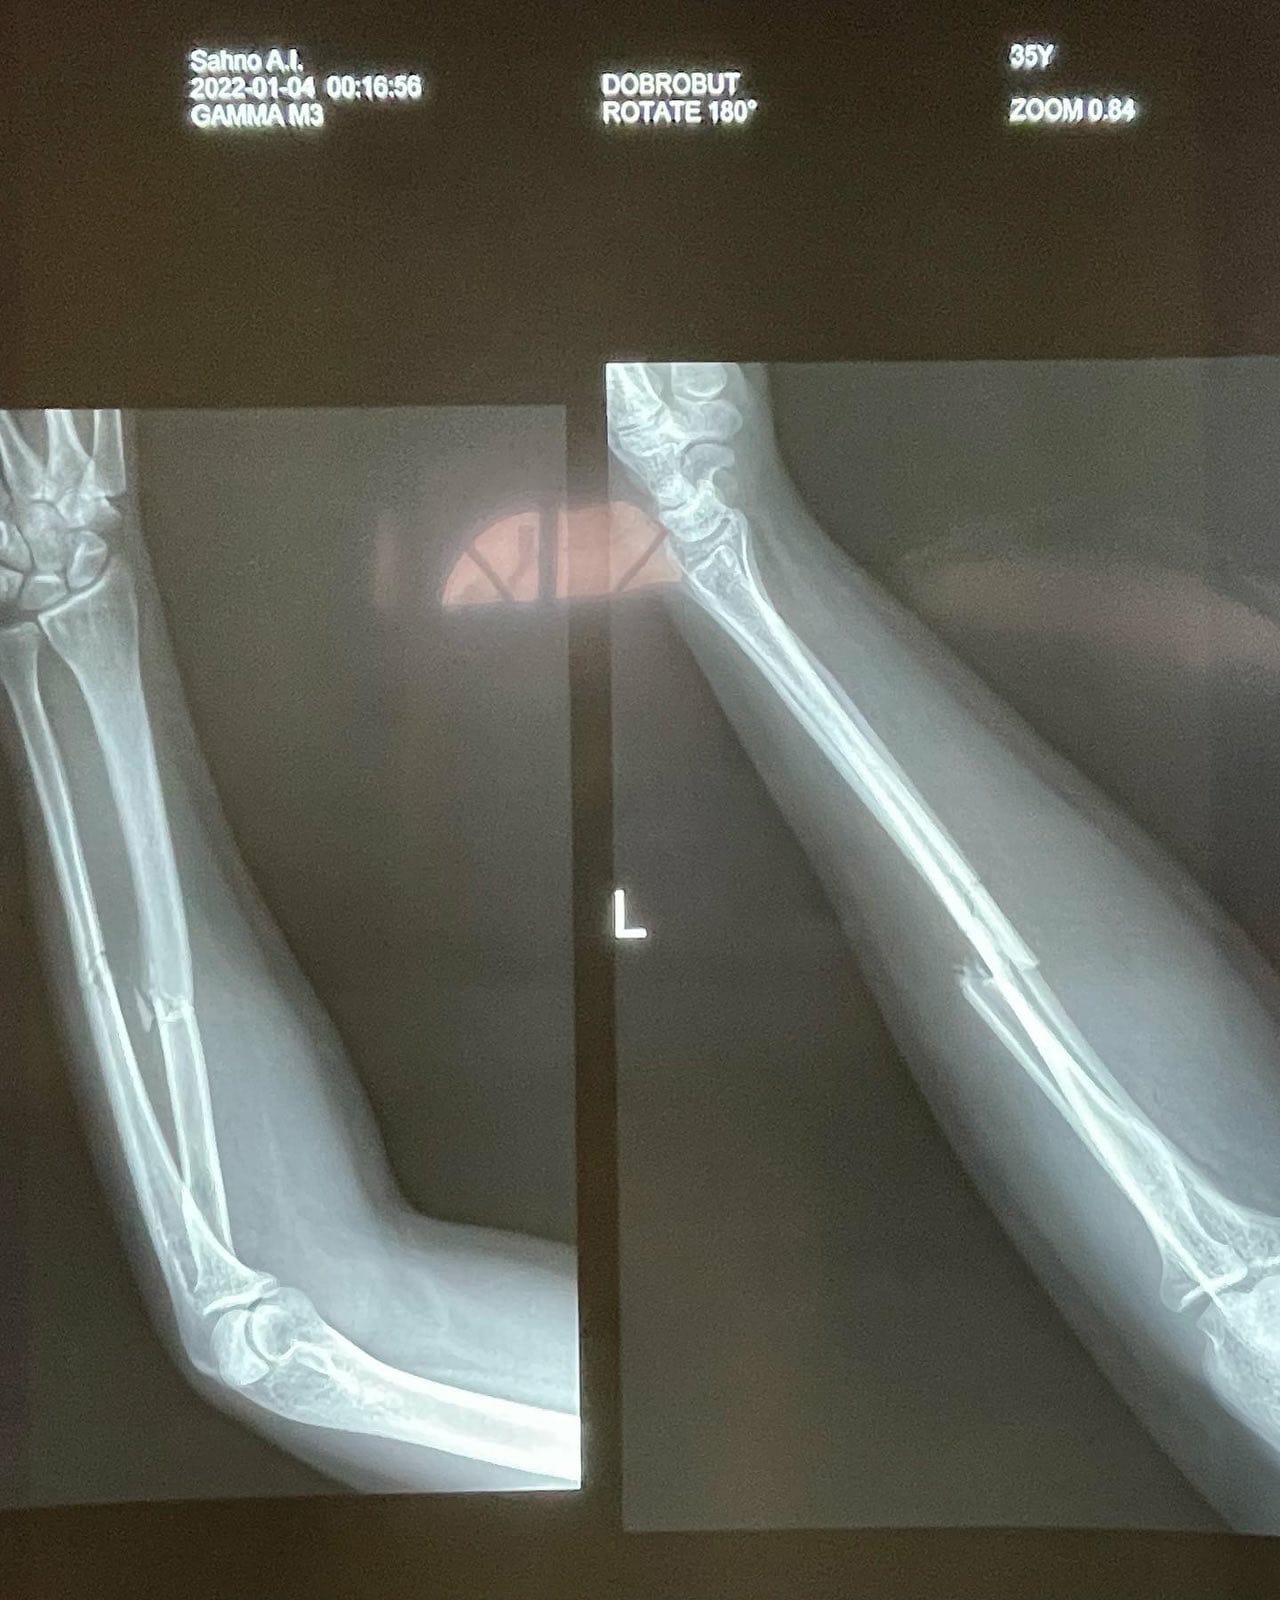

Коррекция при переломах костей после травм